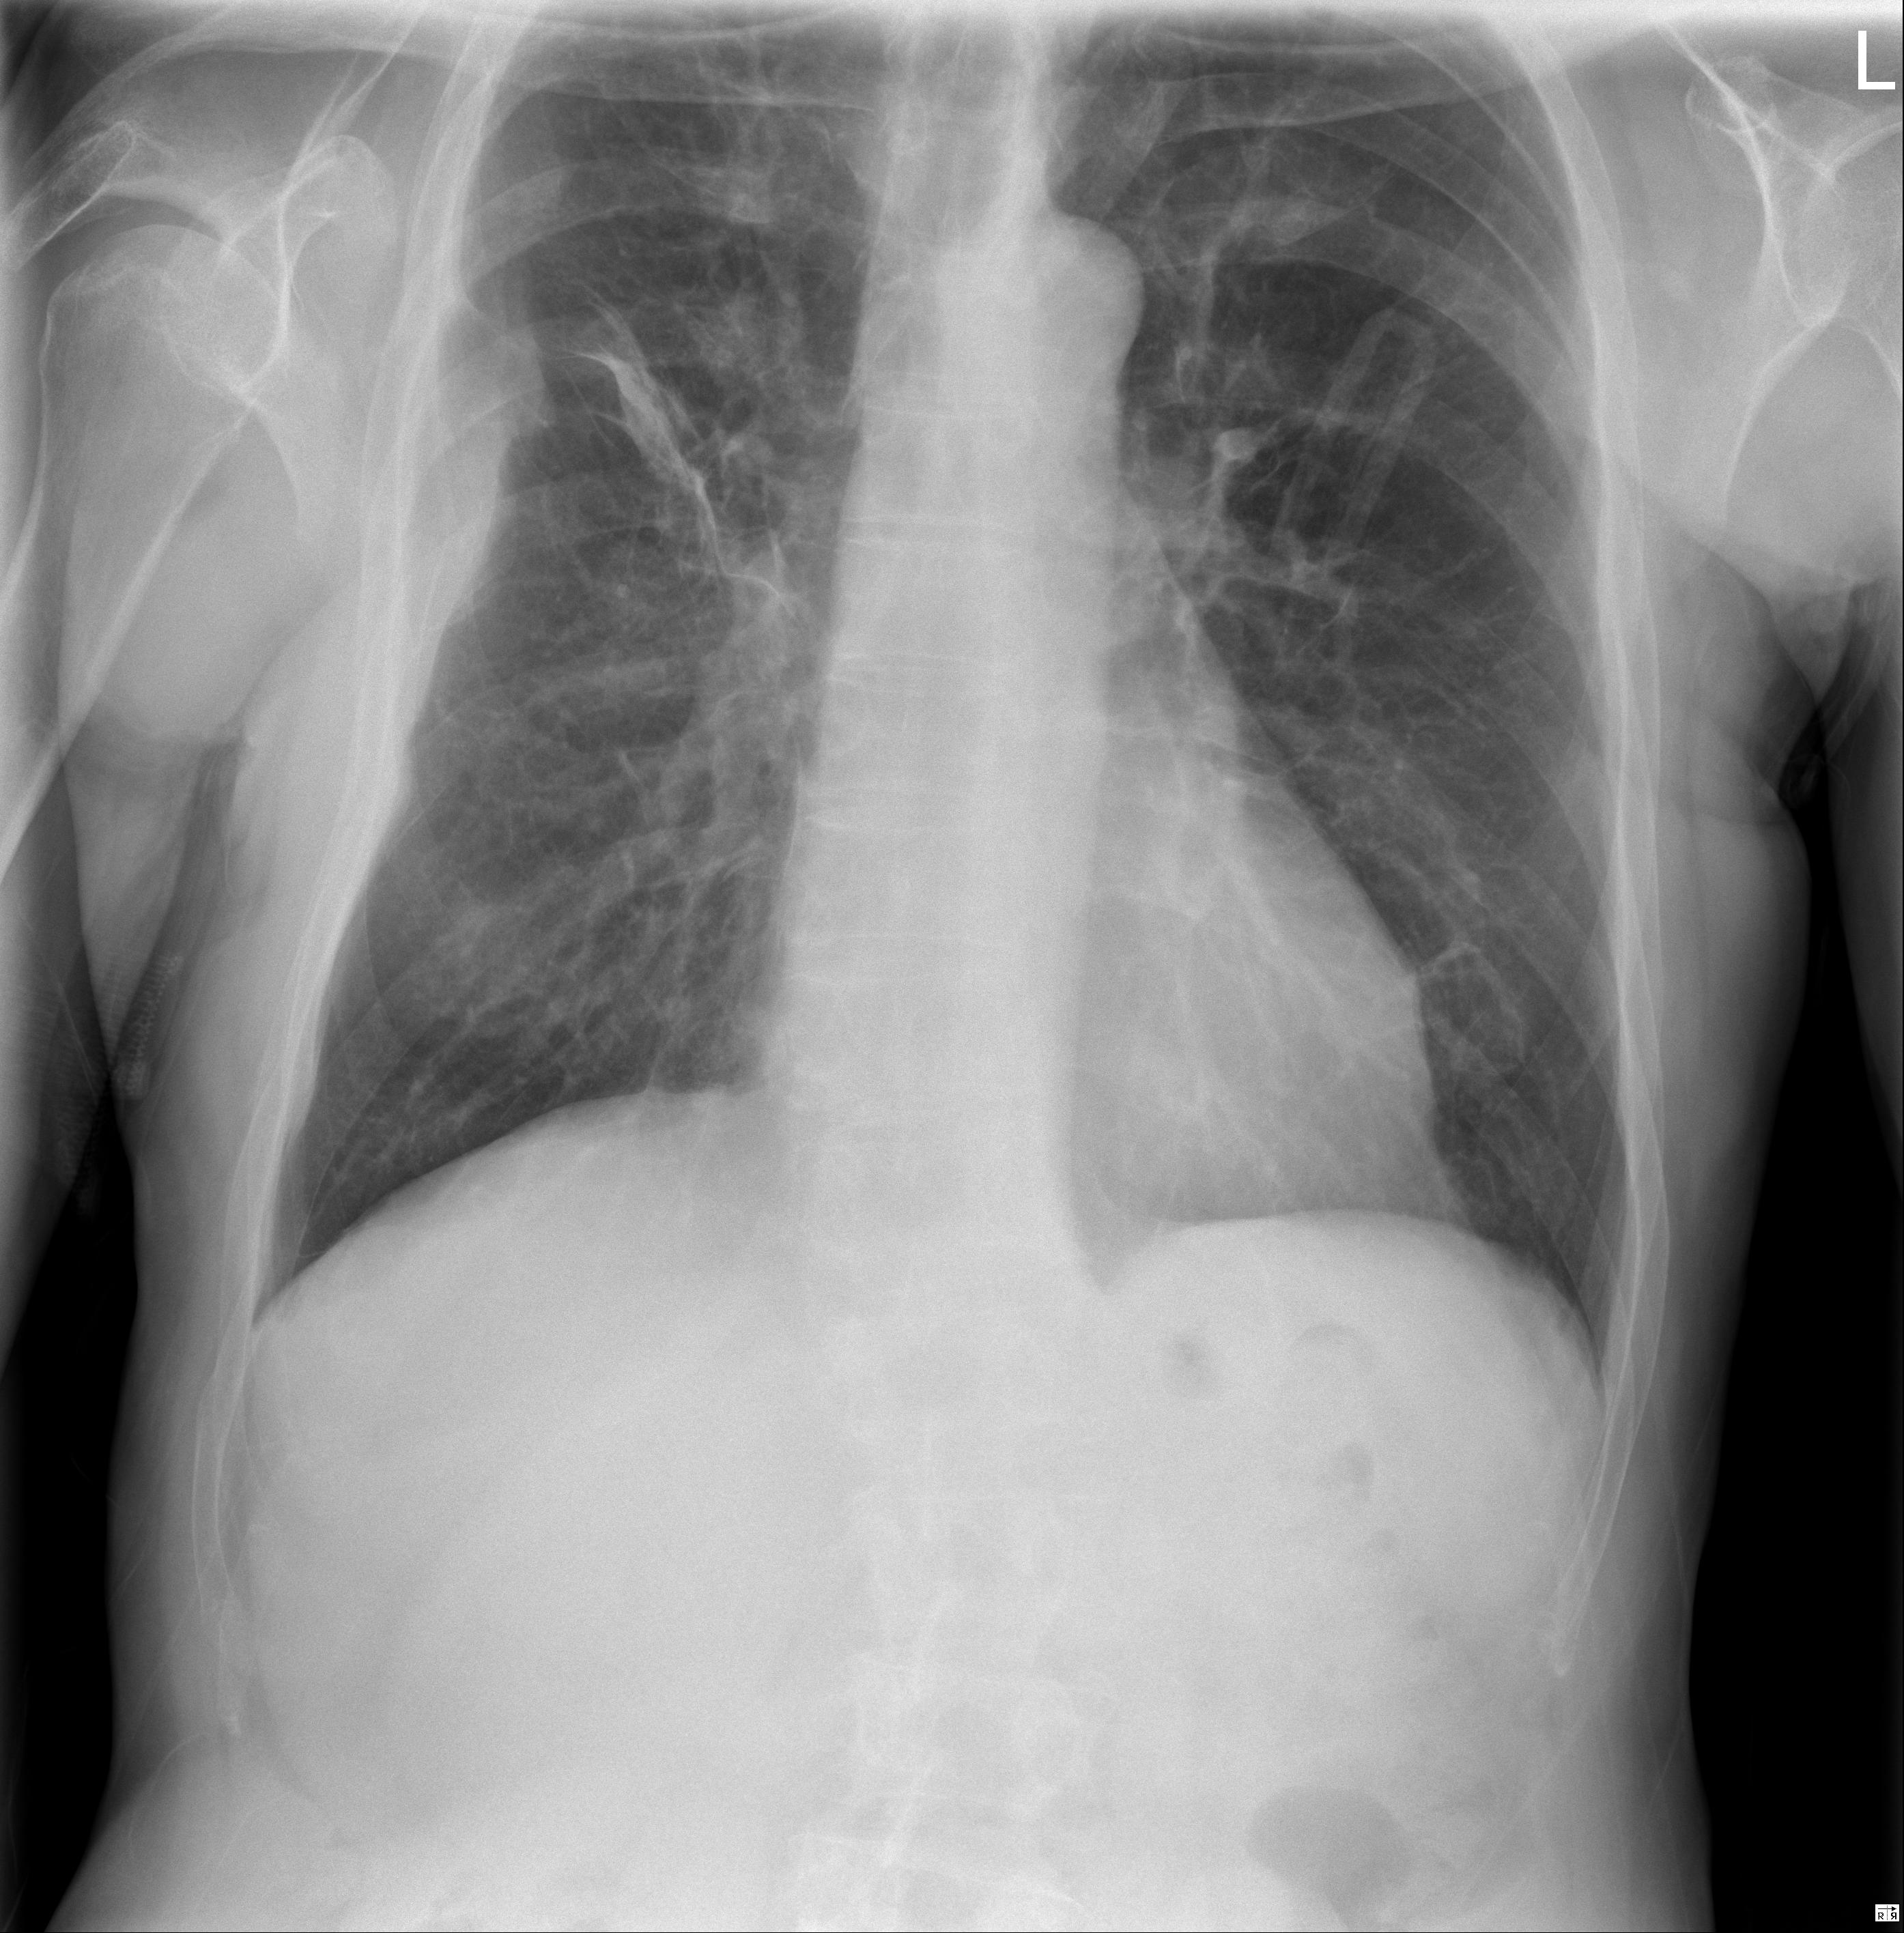

1 Tórax